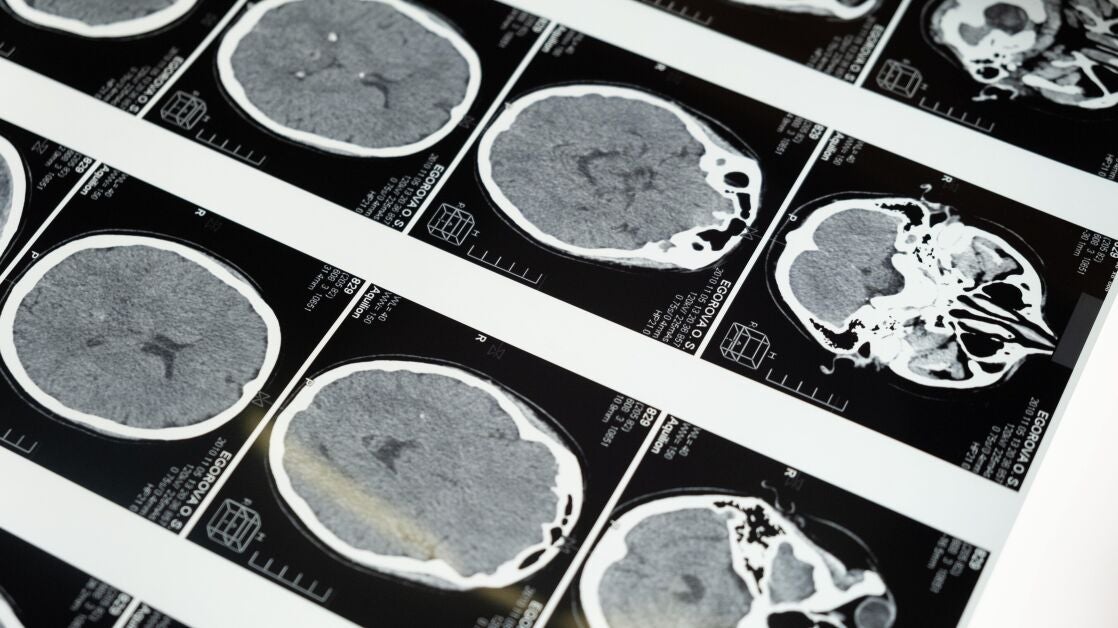

Los síntomas más frecuentes asociados con los tumores cerebrales son: trastornos del comportamiento, crisis epilépticas, vómitos, alteraciones visuales, fiebre, así como fatiga o dolores de cabeza. Además, explican los neurólogos de la SEN, el 80% de las personas presentarán disfunción cognitiva, el 78% disfunción motora y el 37% disfunción en el control de esfínteres.

"Aunque los principales síntomas asociados al cáncer cerebral dependen de la localización del tumor y de la posible inflamación, otros estarán relacionados con los efectos secundarios de la neurocirugía, la quimioterapia, la radiación u otros fármacos empleados para su tratamiento. Y todo ello, repercutirá en la autonomía y calidad de vida de la persona que lo sufre", explica Berta de Andrés, Coordinadora de la Sección de Neurofisioterapia de la SEN.

Es, por lo tanto, "bastante frecuente que personas con tumores cerebrales presenten múltiples síntomas neurológicos y complicaciones sistémicas. Y todos deben ser tratados y reconocidos de forma adecuada", señala la doctora de Andrés. "Puesto que es común que se desarrollen dificultades en el movimiento, en la orientación espacial, apraxia, heminegligencia, déficits sensoriales, en el equilibrio o en la coordinación, las últimas investigaciones apuntan a que el 80% de las personas que los sufren requieren Neurorehabilitación", añade la experta.